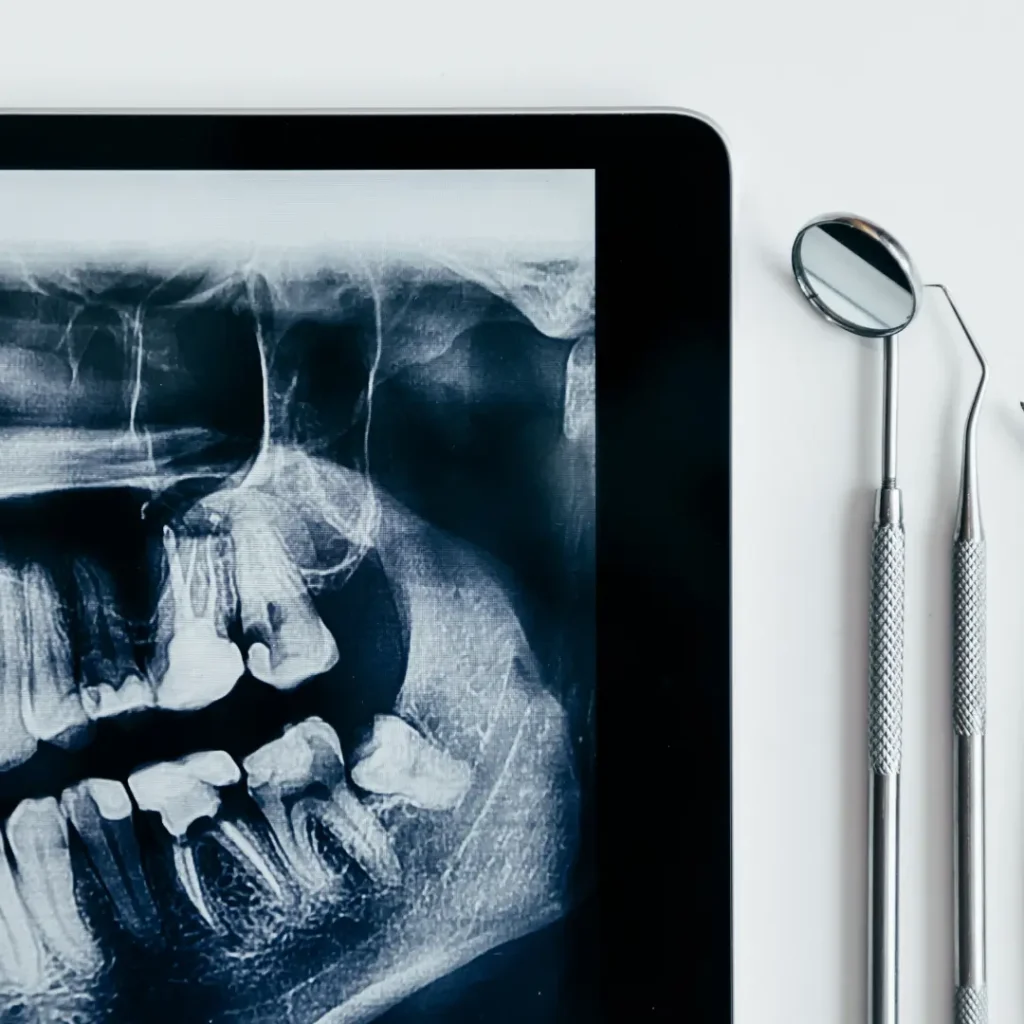

El primer paso en el abordaje de la maloclusión esquelética es un diagnóstico preciso. Las herramientas radiográficas, como las radiografías cefalométricas y las tomografías computarizadas, son fundamentales para evaluar la posición relativa de los huesos y planificar el enfoque terapéutico. La colaboración interdisciplinaria con otros profesionales de la salud, como cirujanos maxilofaciales, es esencial para desarrollar un plan de tratamiento integral y personalizado.